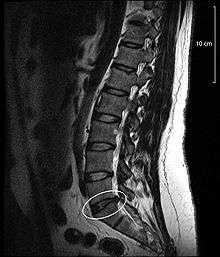

Disc protrusion

Spinal disc protrusion visible in MRI

A disc protrusion is a disease condition which can occur in some vertebrates, including humans, in which the outermost layers of the anulus fibrosus of the intervertebral discs of the spine are intact, but bulge when one or more of the discs are under pressure.

A disc protrusion may progress to a spinal disc herniation, a condition in which there is a tear in the anulus fibrosus.